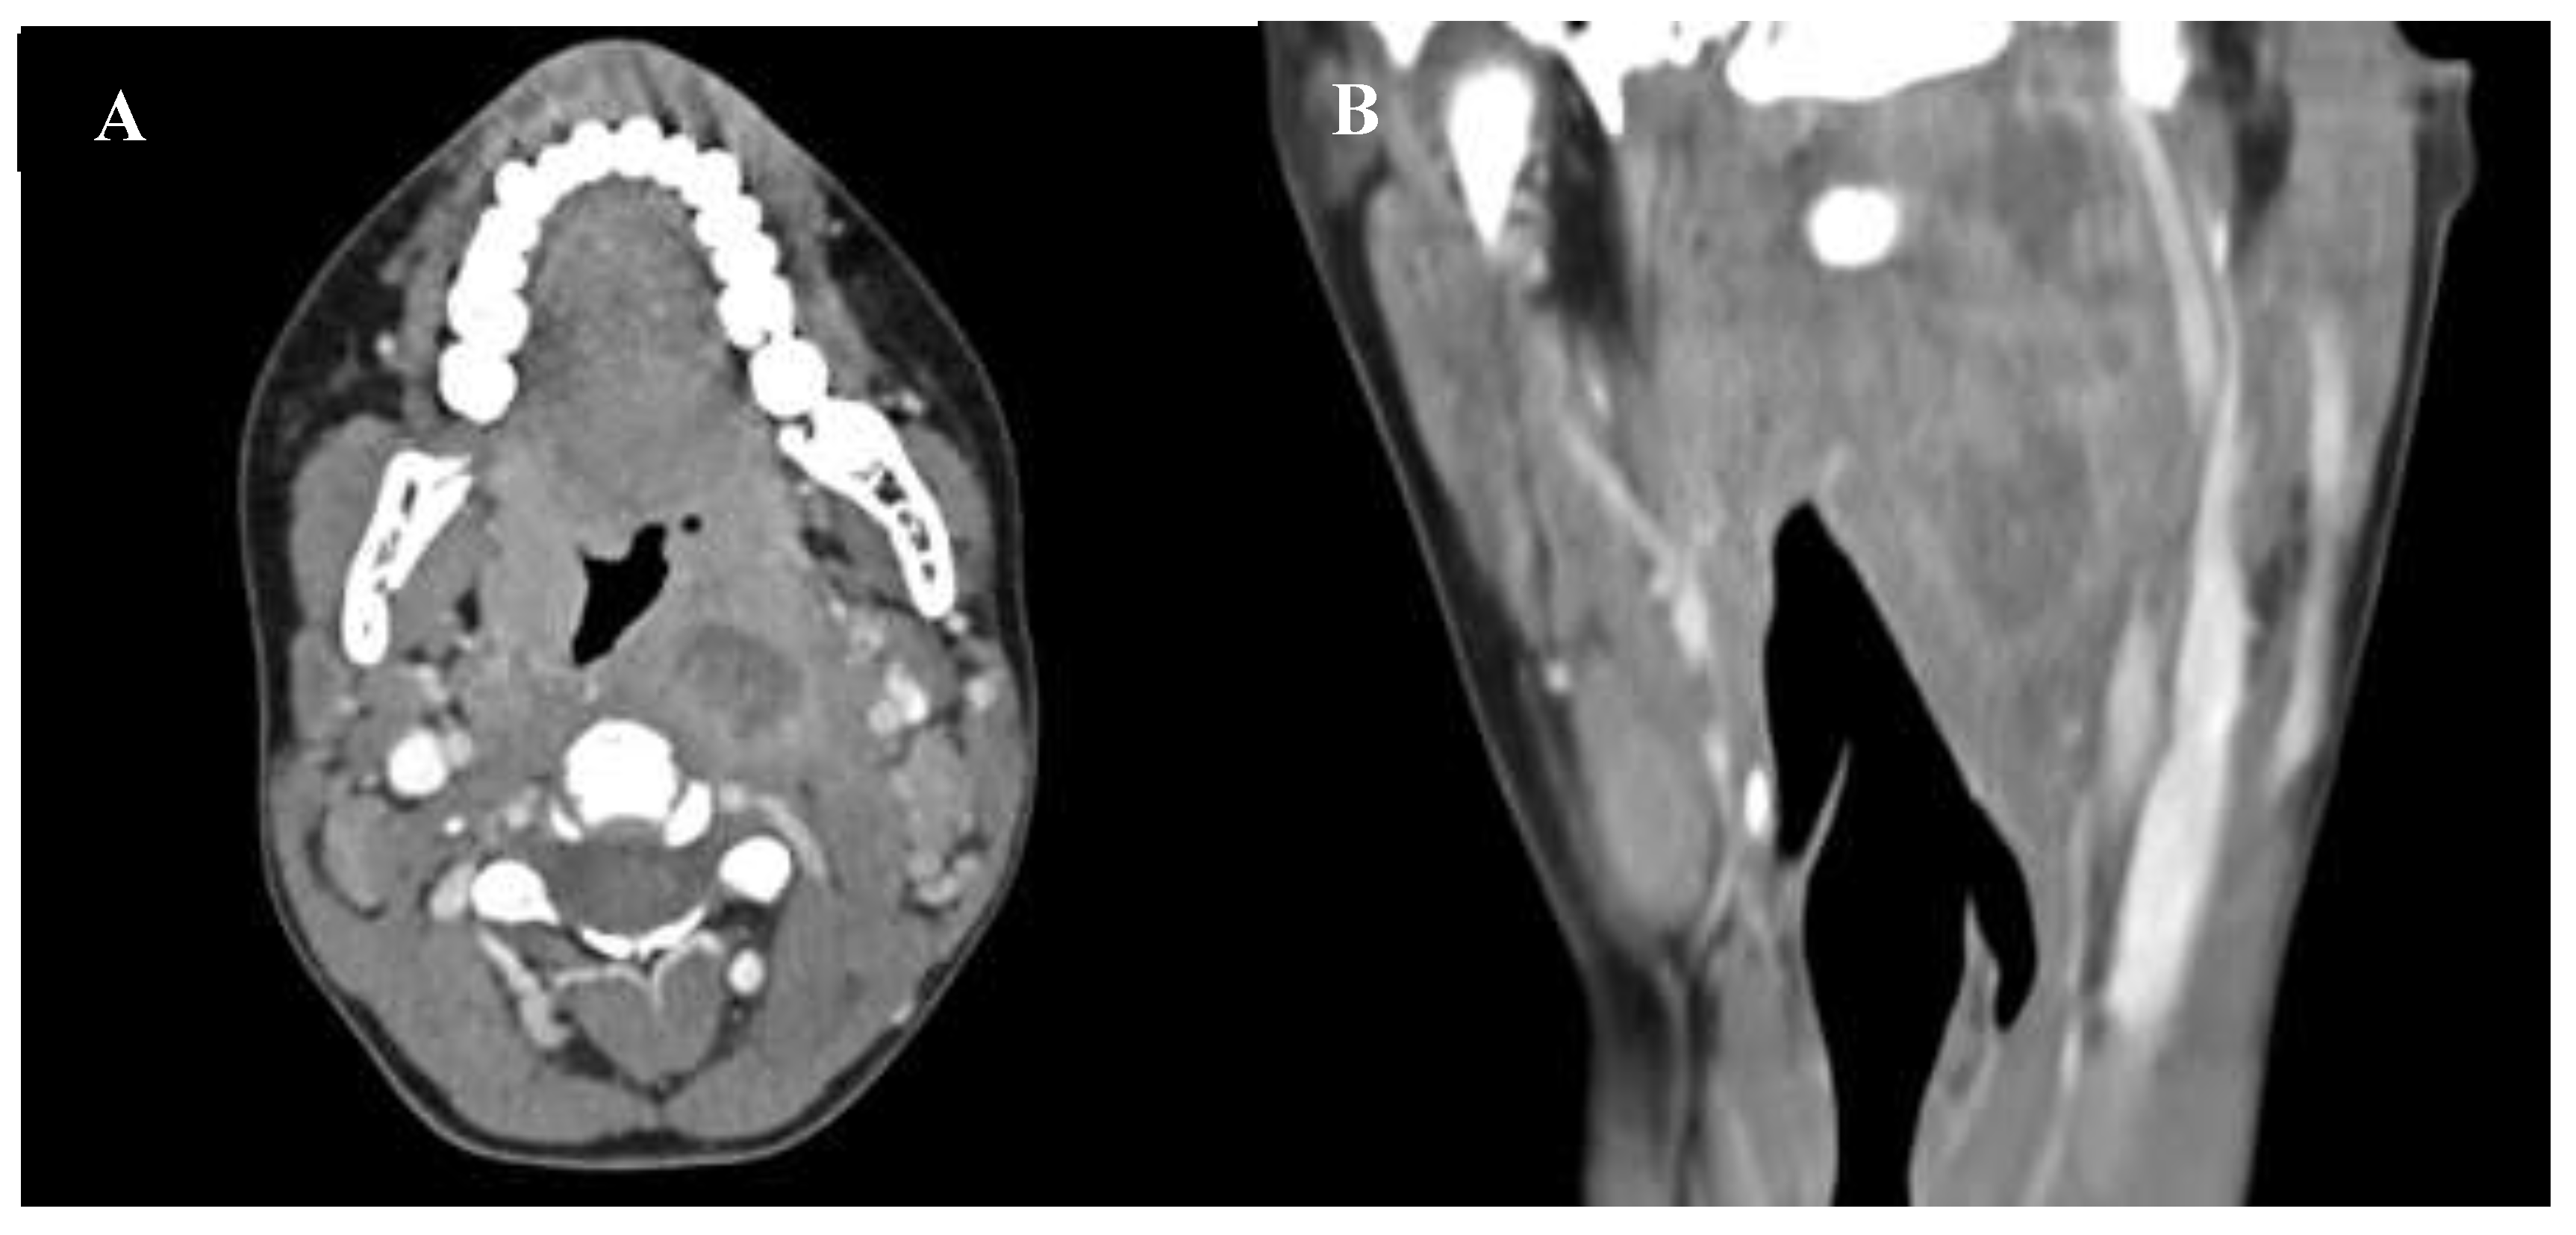

In March 2025 a 16-year-old previously healthy male with a recent diagnosis of EBV-related pharyngotonsillitis presented to the pED with neck pain, pharyngodynia, and intermittent fever persisting for 10 days. ENT evaluation revealed painful limitation of neck movement with mild swelling in the upper left laterocervical region, grade 2 tonsillar hypertrophy, and a left-sided retrotonsillar bulging. Video-laryngoscopy demonstrated swelling of the left oropharyngeal. Given the clinical suspicion of a retro-parapharyngeal asbscess, a contrast-enhanced neck CT scan was performed. Imaging revealed a swelling in the paramedian retropharyngeal space with a hypodense, non-homogeneous central area measuring ​​approximately 16x24 mm on the axial plane and 59 mm in the craniocaudal direction. The mass protruded into the airway, displacing the left palatine tonsil anteromedially and extending toward the superficial neck, compressing the jugular vein (Figure 2).

Figure 2. Axial (A) and coronal (B) CT scan revealed a retropharyngeal abscess protruding into the oropharyngeal lumen.